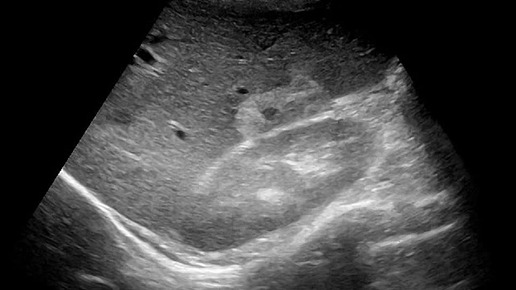

Видео к статье "множественные гемангиомы печени". https://dzen.ru/a/Z-t2fs4nxn0nGO2I

Ультразвуковые находки от врача УЗД Зорина Я.П.